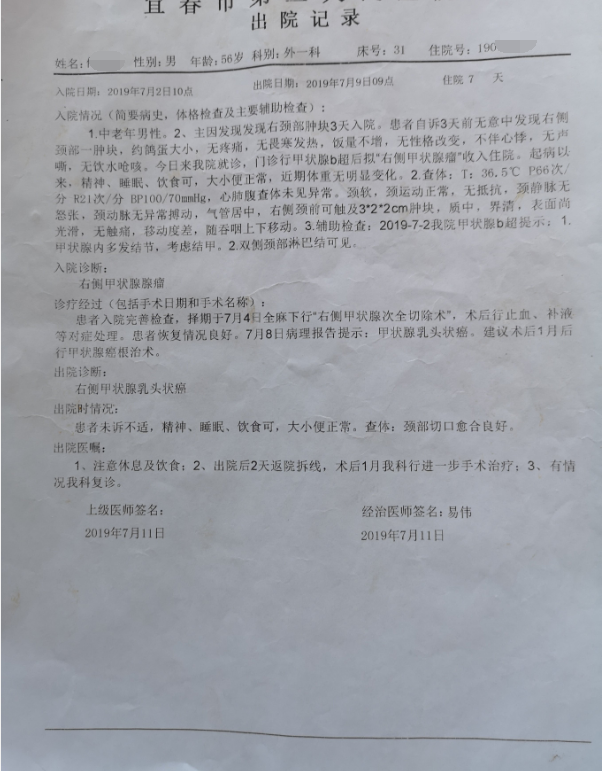

甲状腺癌再次手术

病例2 右2,右4R区,左6区残留,颈部切口清扫,未开胸